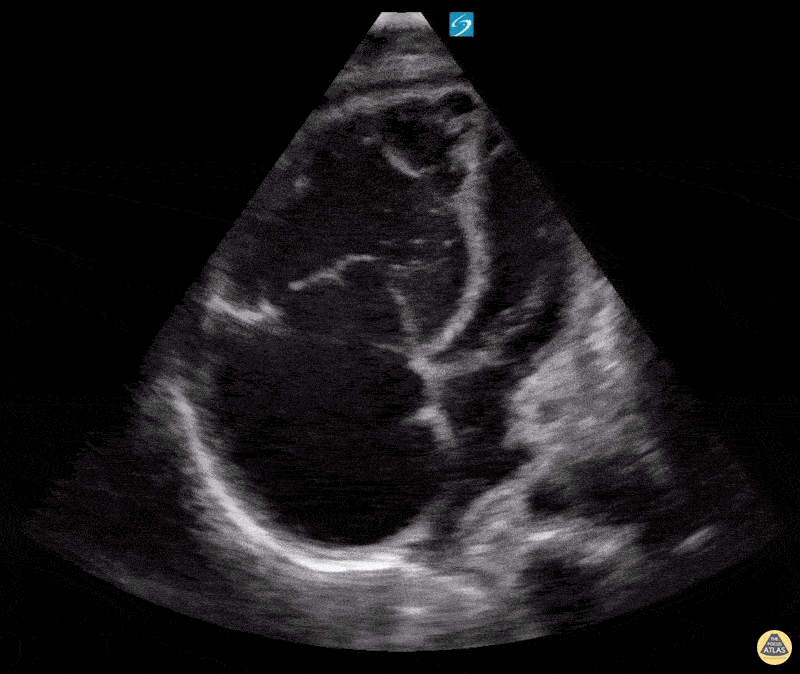

Right Ventricular Dysfunction - Right Heart Strain in Pulmonary Hypertension A4C

28 yo M PMH Pulmonary Hypertension (PH) group 1 and 4, RV failure due to PH, invasive pulmonary aspergillosis in MICU for mixed shock (Cardiogenic vs Sepsis). Lethargic with high needs for Heated High Flow Nasal Canula. RV failure is noted with significant RV and RA dilation with bowing of interventricular septum into LVOT as well as McConnell's sign. Patient also has a pericardial effusion, bilateral pleural effusions and ascites. Erick Otiniano, MD MPH | DHREM PGY1